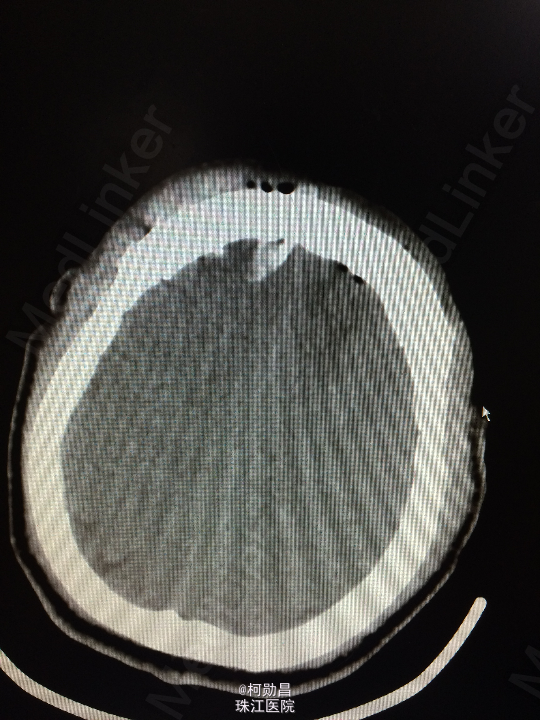

主诉:头痛伴左眼视力下降半年 病史:患者46岁男性,缘于半年前无明显诱因出现头痛,当时未予特殊处理,后症状进行性加重,并发左眼视力下降,于当地医院行头颅CT及MR检查提示颅内占位,为进一步治疗而入我院。 既往病史:5年前曾患鼻咽癌

查体:神志清楚,对答流利,左侧眼裂变小,左侧瞳孔散大,直径4mm,对光反射迟钝,左眼视力下降。右侧正常。 辅助检查:头颅MR提示前颅底筛沟通病变

诊断:鼻咽癌脑转移 处理:全麻下行颅筛沟通占位切除术,术后病理提示:鼻咽非角化鼻咽癌脑转移